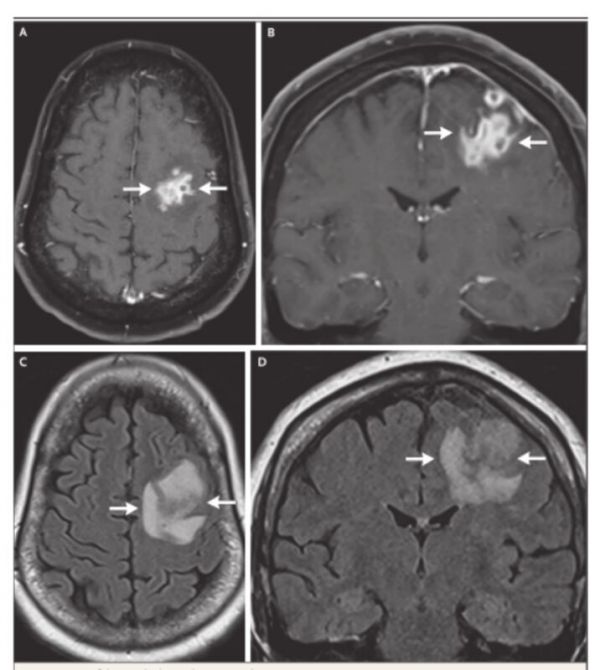

白细胞计数升高,MRI如图。

患者老年女性,急性起病,有意识水平下降,既往重症肌无力病史,结合WBC升高、核磁所示不规则环形强化及周围大水肿带,优先考虑脑脓肿,需完善腰穿和CSF病原学检查。因MG可合并纵膈肿瘤,需鉴别转移瘤。

结合影像学表现,高度怀疑是淋巴瘤,进行了开颅活检,术中冰冻切片并么有提示炎症,也提示有恶性浸润,考虑淋巴瘤,取了组织送病检,没有取额外组织做微生物检测。

术后,尽管接受了糖皮质激素治疗,患者的神经系统状况仍持续恶化,术后第一天,重复头部 MRI 检查显示病情进展,水肿加重。